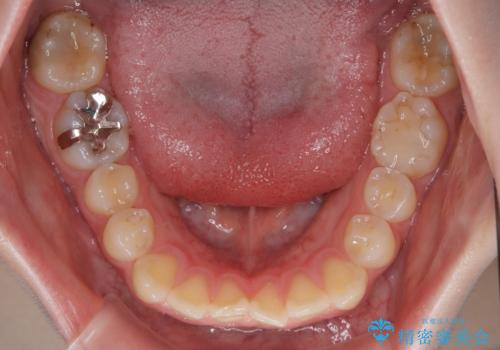

- 上下前歯部のデコボコを気にして来院された患者様です。

叢生が軽度であったため、僅か半年で装置を除去することができました。